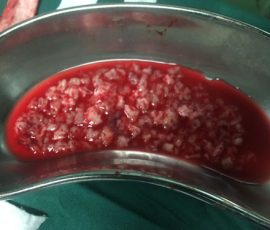

- نمونه برداری از بافت مغز برای تعیین نوع تومور

جراحی

یکی از رایجترین روشهای درمان تومور مغزی، جراحی است که با هدف برداشتن کامل یا حداکثر بخش ممکن از تومور انجام میشود. انتخاب بهترین جراح تومور مغزی میتواند تاثیر زیادی بر بهبود وضعیت بیمار و کاهش علائم داشته باشد. میزان امکان برداشت تومور به محل آن در مغز و نزدیکی به نواحی مهم بستگی دارد، و جراح با دقت فوقالعاده کار میکند تا کمترین آسیب به بافتهای سالم وارد شود. در بسیاری از موارد، جراحی به کاهش فشار بر مغز و بهبود علائم کمک قابل توجهی میکند.